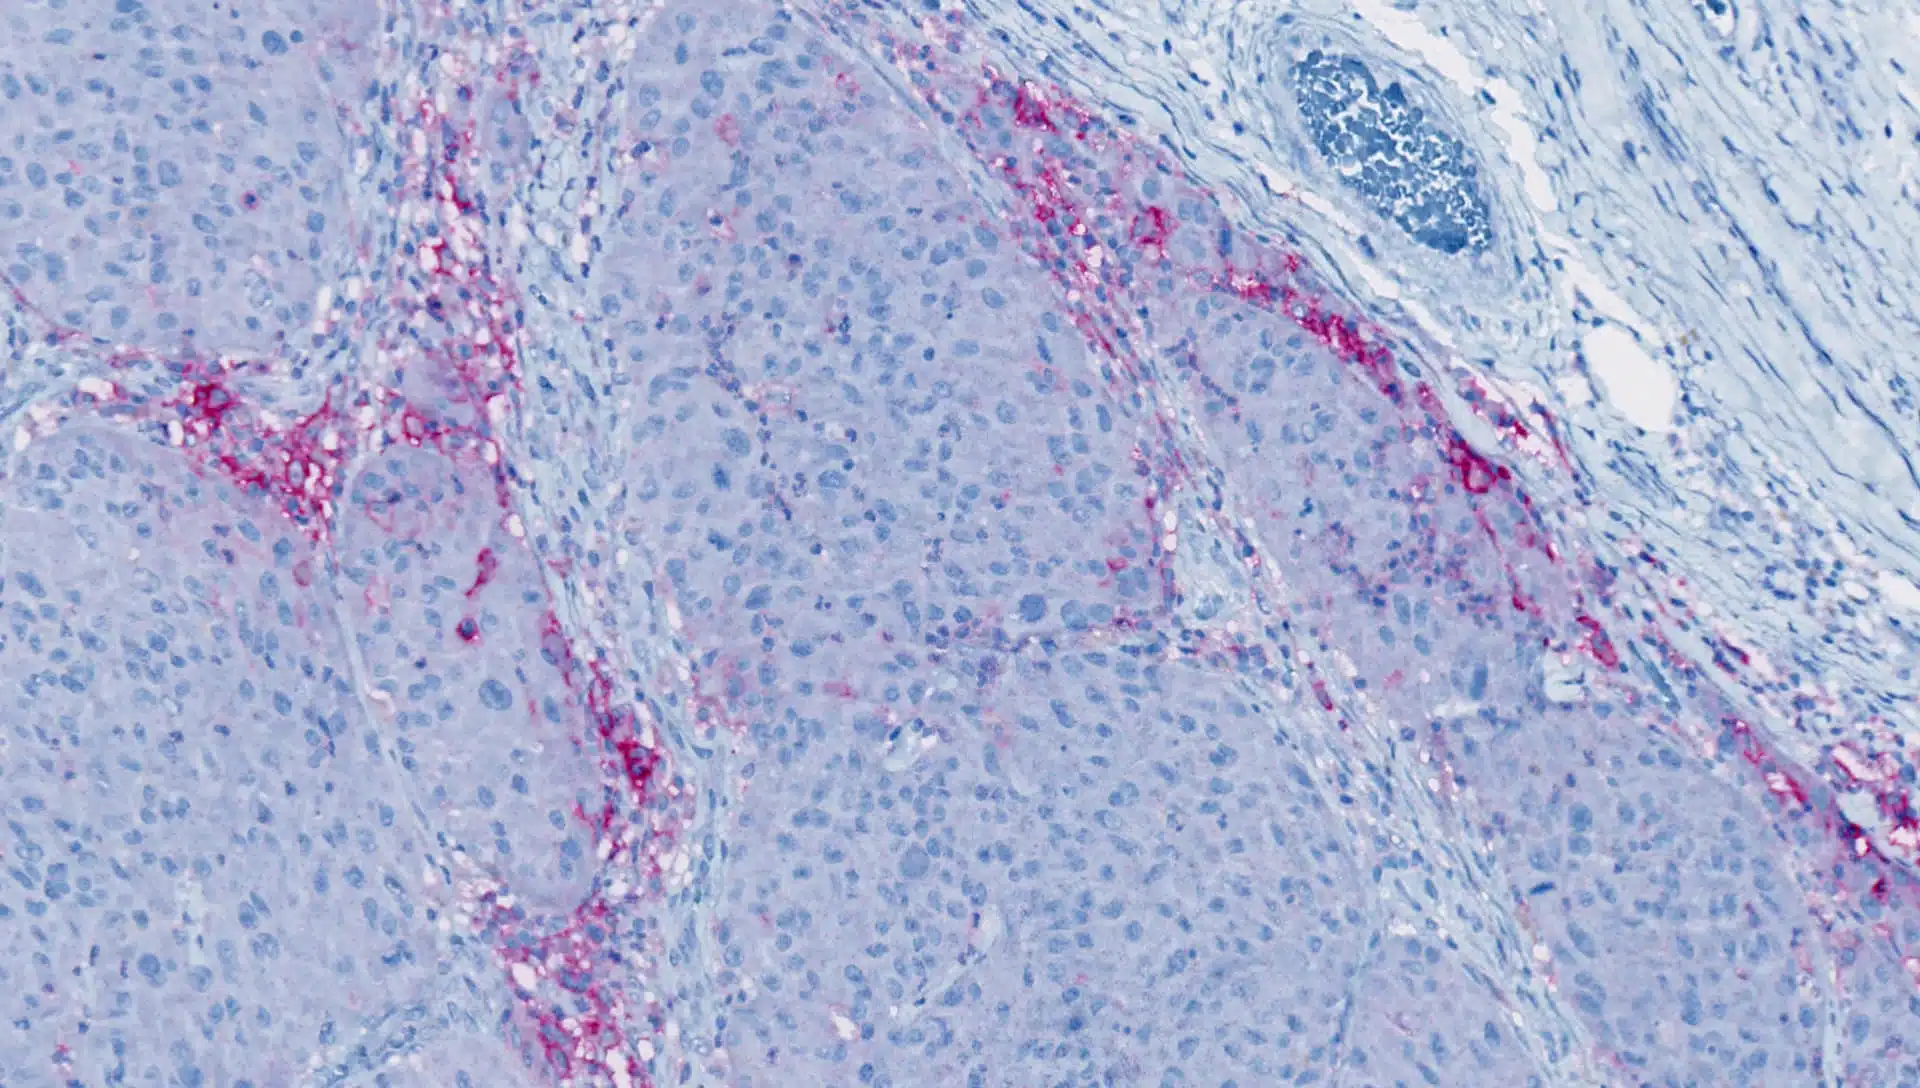

HBRI HISTOPROFILE® Multiplex IHC panels

HBRI offers both custom multiplex development and validation, as well as panels that come already validated for specific indications.

- Tissue resident memory T-Cells CD8/CD49a/CD3/CD68/CD103

- Dendritic cells langerin/CD1a

- T-cell activation CD8/Ki-67/GranzymeB

- T-reg Light CD3/CD8/FoxP3

- PD-L1 CD68/panCK/PD-L1

- Checkpoint inhibitors CD3/CD8/PD-1/PD-L1/Custom

- Neuro macrophage CD68/CD163/GFAP/TMEM-119/c-maf